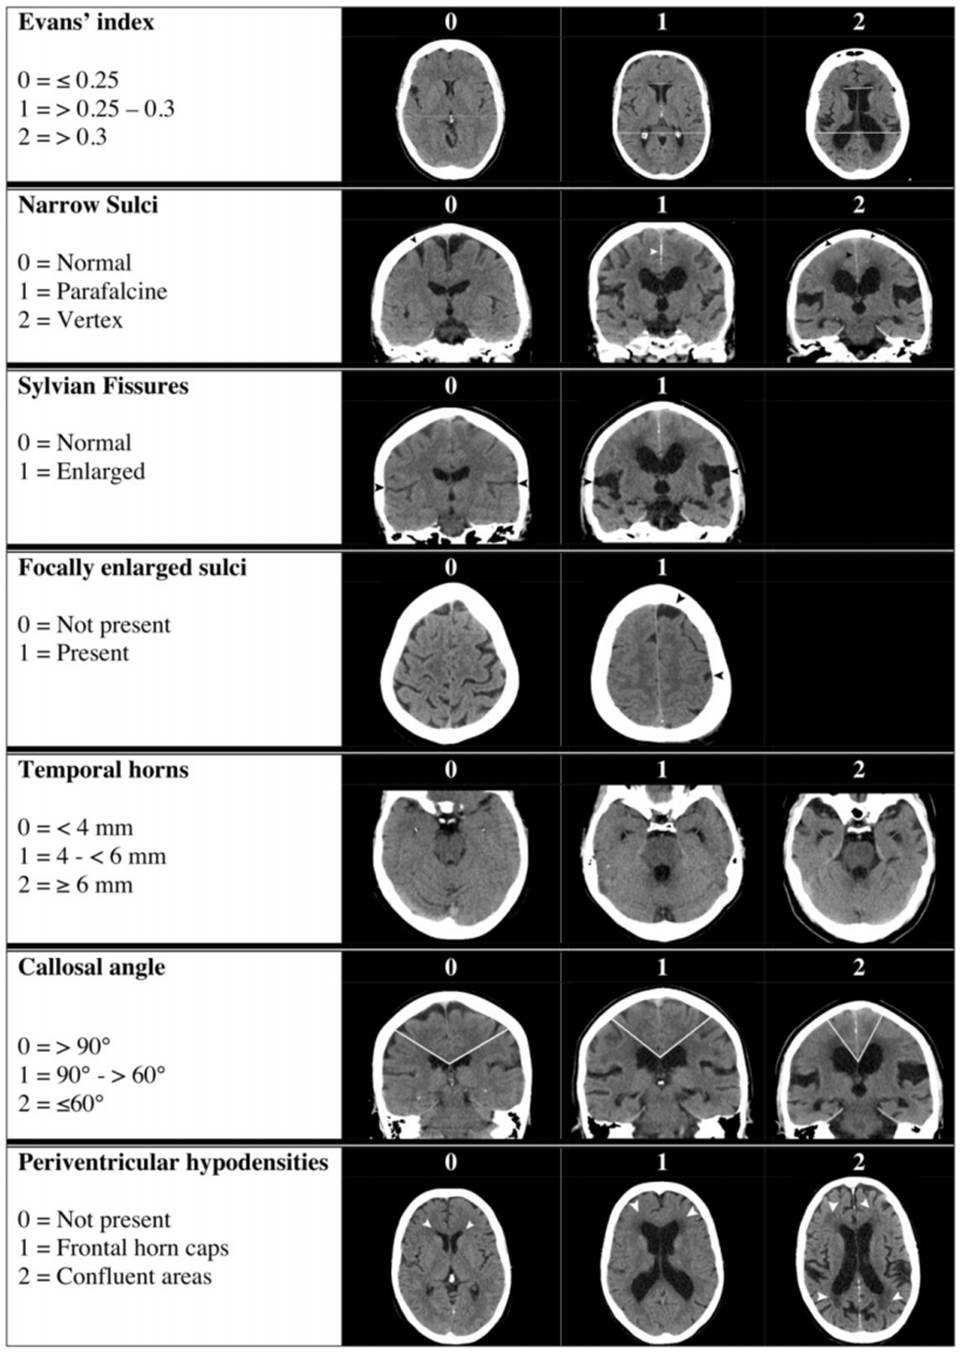

NPH Radscale

score

Score >4 predicts higher chance of shunt responsive NPH

(From Kockum et al Plos One 2020)

Evans index

o Ratio of the widest width of the frontal ventricles to the widest width of the brain on an axial plane

Angle of corpus callosum on coronal imaging

DESH Dilated epidural spaces in hydrocephalus

Transependymal oedema